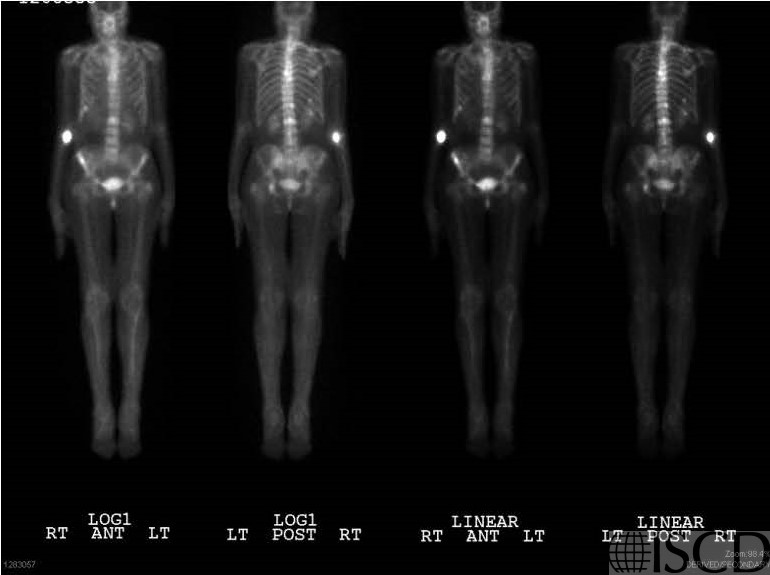

This is the nuclear medicine scan. The biopsy- proven diagnosis was metastatic breast cancer.

This case shows a DXA scan, with a follow-up scan 4 years later showing a sclerotic L2 and large increases in bone mineral density. This ultimately was proven to be metastatic breast cancer. The accompanying radiograph and nuclear medicine scan are also included.